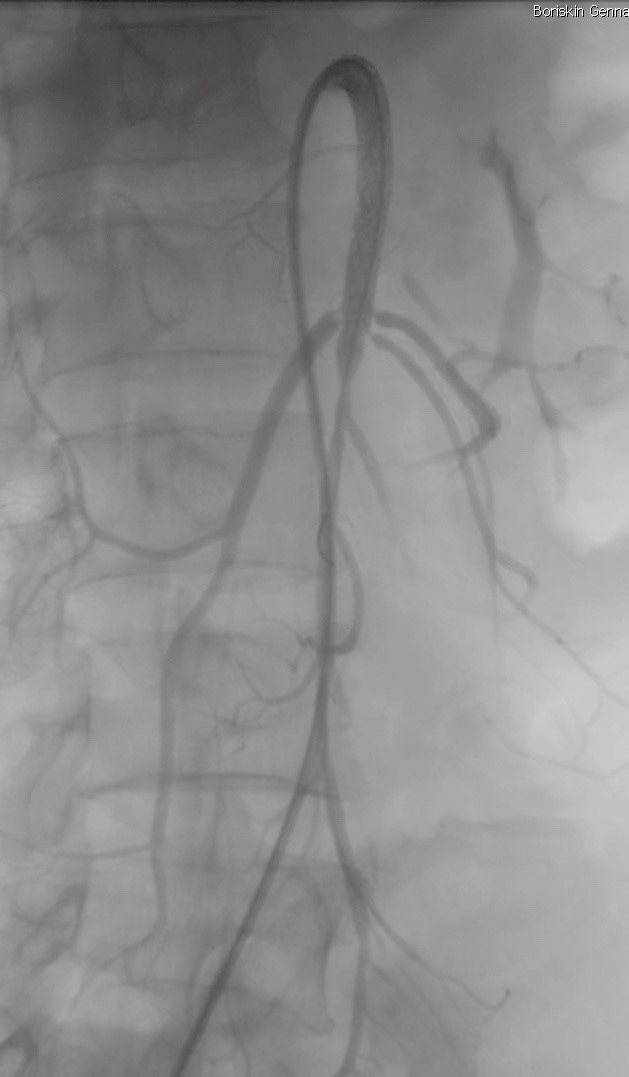

12.01.2017г в экстренном порядке пациент прооперирован: Правым трансфеморальным доступом выполнена ангиография висцеральных ветвей брюшного отдела аорты, на которой выявлена тромботическая окклюзия верхней брыжеечной артерии (ВБА) (рис. 2). Через установленный в ВБА проводниковый катетер JR7F в несколько этапов выполнена аспирационная тромбэктомия, с извлечением тромботических масс, (рис. 3). На контрольной ангиографии признаки субокклюзирующей диссекции и тромбоза в проксимальной трети ВБА (рис. 4). Выполнена имплантация стента Assurant Cobalt 7,0X60 мм, в пораженный участок ВБА (рис. 5). На контрольной ангиографии получен удовлетворительный непосредственный ангиографический результат, признаков тромбоза и диссекции нет (рис 6). Медикаментозная поддержка чрезкожного вмешательства проводилась по стандартной схеме лечения больных острым коронарным синдромом клопидогрель 600 мг и аспирин 300 мг внутрь однократно, 100 ед./кг гепарина интраартериально. Анестезиологическое обеспечение ограничилось нейролептаналгезией. Время эндоваскулярной интревенции составило 32 минуты. Время рентгеноскопии 14 минут. В течение суток больной находился под наблюдением в РАО. В раннем послеоперационном периоде отмечается купирование болевого синдрома. Спустя 24 часа после восстановления кровотока в верхней брыжеечной артерии выполнена диагностическая лапароскопия, при котором признаков некроза кишечника не выявлено.

Рисунок 2. Ангиографическая картина тромбоза ВБА

Рисунок 3. Контрольная ангиографии: признаки субокклюзирующей диссекции и тромбоза в проксимальной трети ВБА